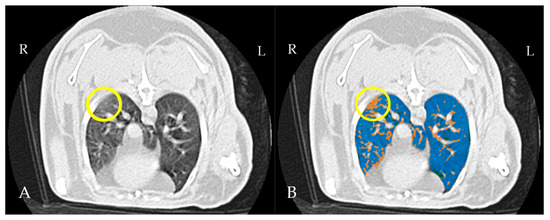

4.3. Thoracic CT